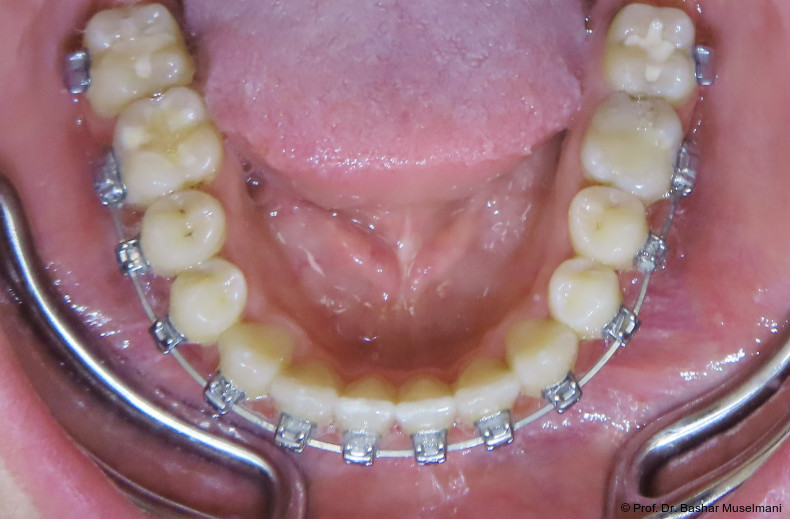

Die Abbildungen 1 bis 3 zeigen die initiale klinische und radiologische Ausgangssituation.

Apparative Versorgung

Die Behandlung erfolgte mittels einer festsitzenden Multibracketapparatur unter Verwendung passiver selbstligierender Brackets (Damon Ultima System) im Ober- und Unterkiefer.

Bracketpositionierung und Torque-Strategie

Oberkiefer

• Zähne 12–22: Brackets mit Retroklinations-­Torque

• Zähne 13 und 23: Brackets mit proklinationsförderndem (Brocline-)Torque

Ziel war die kontrollierte Retrusion der oberen Front bei gleichzeitiger Sicherung der Eckzahnbreite.

Zu Beginn der Nivellierungsphase wurden in beiden Kiefern 0.013" CuNiTi-Bögen eingesetzt (Abb. 4a–e).